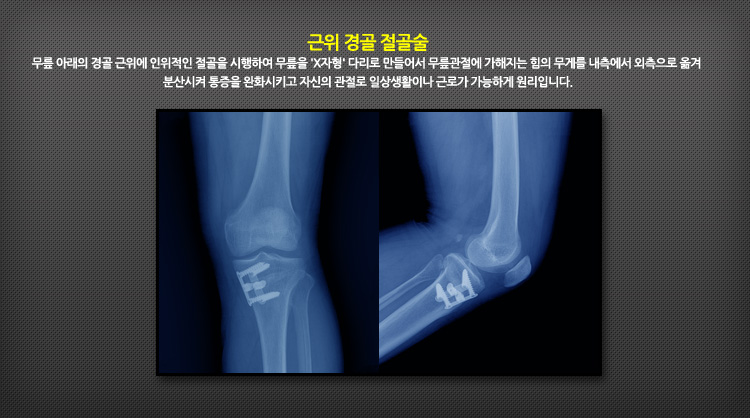

아래의 그림은 근위 경골 절골술은 무릎 아래의 경골 근위에 인위적인 절골을 시행하여 무릎을 'X자형' 다리로 만들어서 무릎관절에 가해지는 힘의 무게를 내측에서 외측으로 옮겨 분산시켜 통증을 완화시키고 자신의 관절로 일상생활이나 근로가 가능하게 원리입니다.